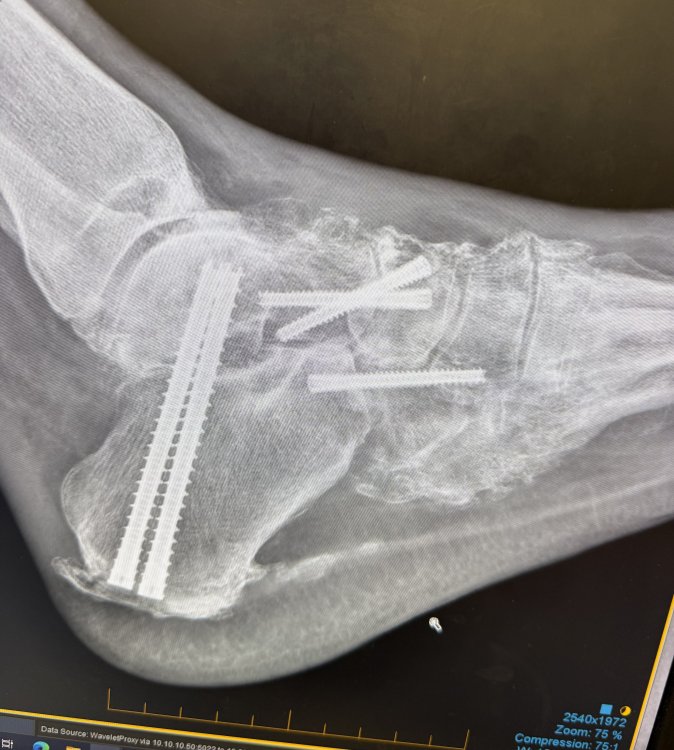

Ashley D Austin Posted October 3 Posted October 3 (edited) I have had foot surgery and the bone in my foot is now permanently higher than it was before and it is very painful to wear any type of closed leather shoe or boot. Soft hiking boots and sneakers are much more comfortable. This spring, I attended a state match and was told I had to wear "cowboy boots". I looked around and saw men wearing leather and soft lace-up shooting boots (which are not cowboy boots), lace-up soft hiking boots, sneakers (tennis shoes), and one that was wearing black socks and black sandals. I am not complaining about being singled out, but I would like a definitive answer from SASS about what the official determination is on footwear for age-based categories? Edited October 3 by Ashley D Austin 2 Quote